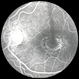

- chloroquine toxicity